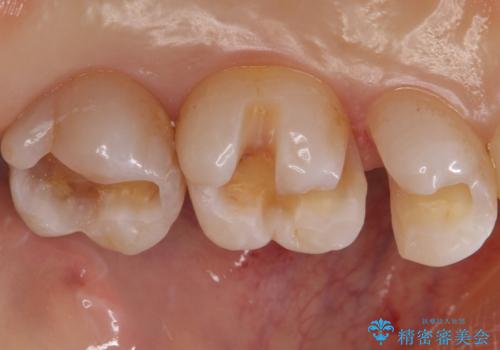

銀歯を白くしたい セラミックインレーでのやり替え

- 銀歯を白くしたいとのことで来院されました。

特に大きな虫歯もなかったため、周りの歯を残しつつセラミックインレーでの修復処置をしていきます。